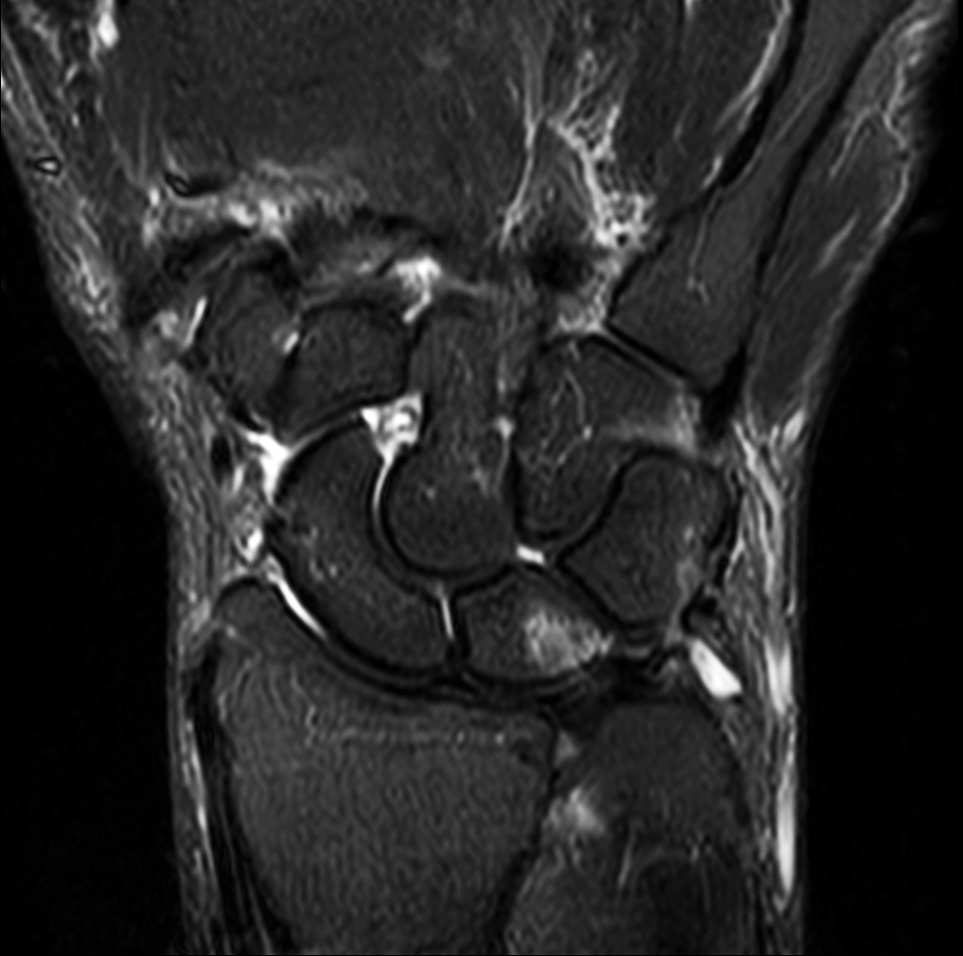

Comprehensive wrist imaging